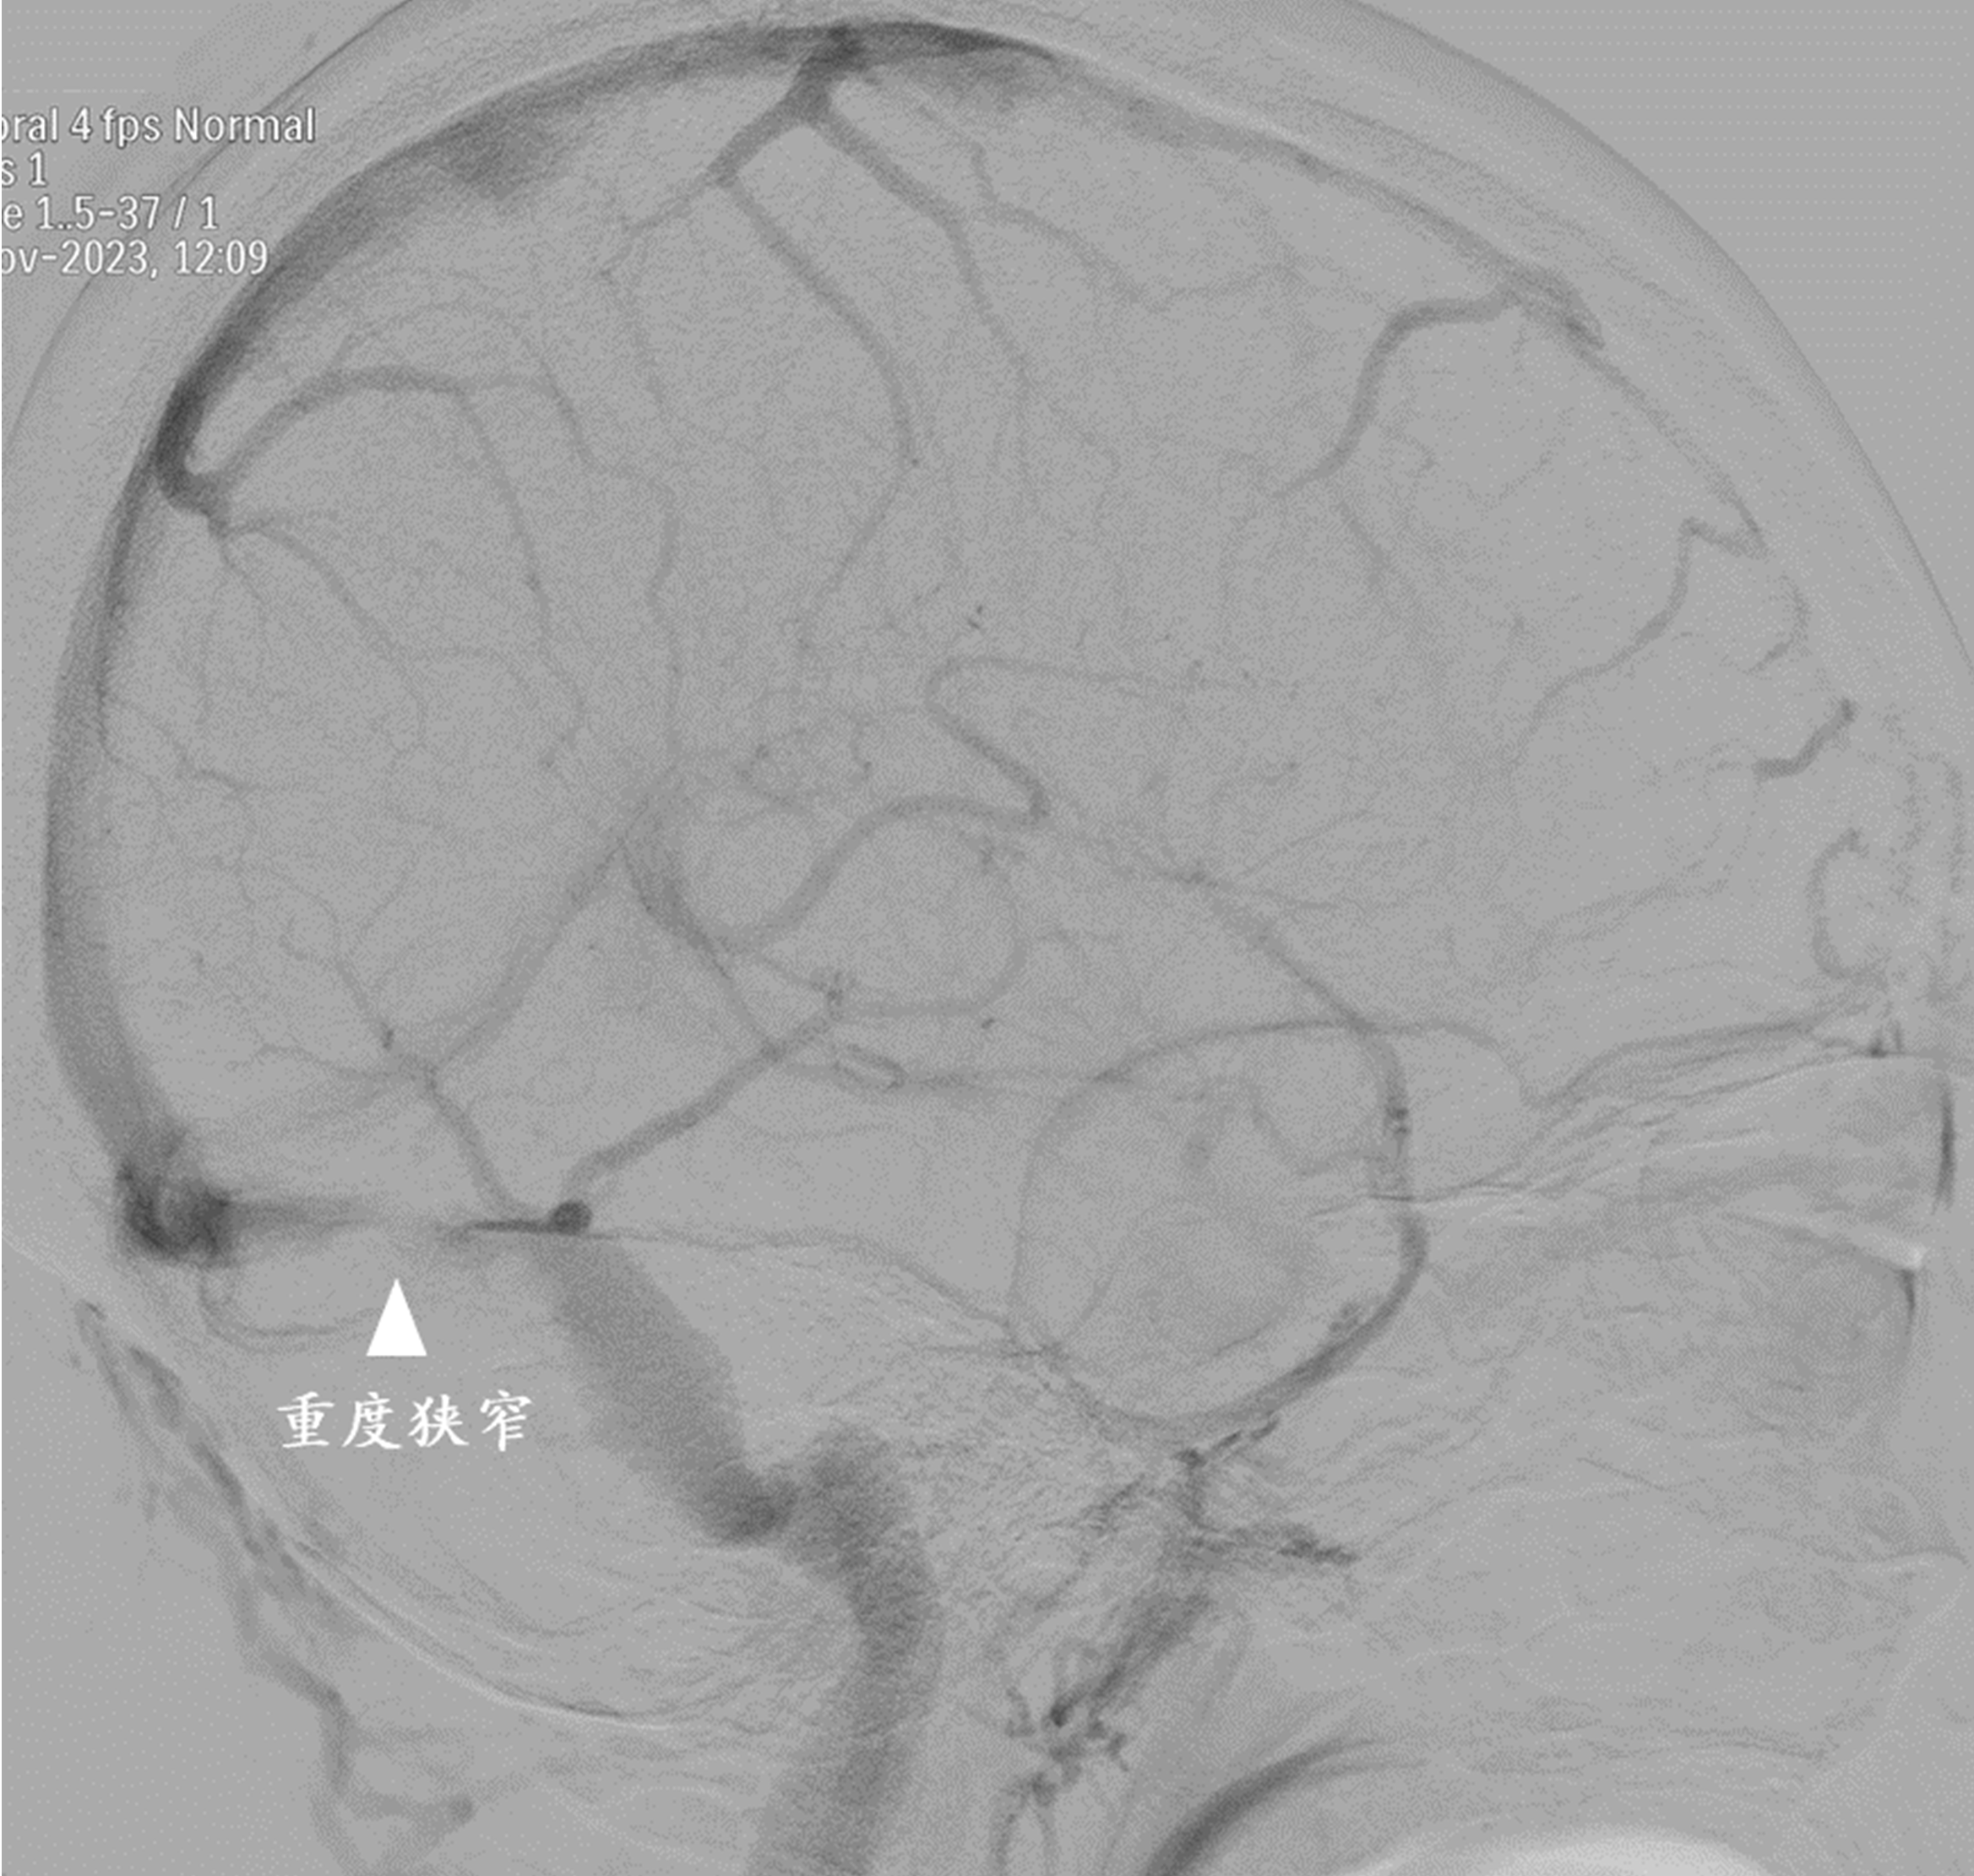

38岁吴女士五年来一直饱受慢性头痛的煎熬。近一年来,她的头痛症状越来越严重,右眼视力下降,左手麻木乏力,慕名来到上海交通大学医学院附属仁济医院就诊。神经内科主治医生林岩和眼科副主任医生闫焱认为,吴女士的头痛不简单。果然,在进行一系列检查和腰穿后,医生们发现,吴女士存在颅内压增高和眼底异常,头颅磁共振静脉成像显示右侧静脉横窦严重狭窄。于是神经内科、神经外科、眼科和放射科等多个学科的专家立即进行了会诊,大家认为优势侧横窦严重狭窄可能是引起高颅压的原因。

手术中,神经外科副主任医生赵兵准确判断血管狭窄的位置,测量静脉窦狭窄的压力差超过11毫米汞柱,证实了静脉窦狭窄是导致患者种种不适症状的根源。